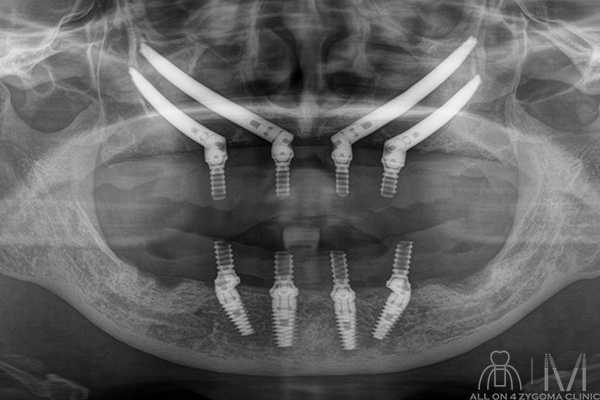

両側上顎は前臼歯歯槽骨に十分なボリュームがないが、頬側に十分なスペースの確保が見込めた。下顎は菲薄な部位はあるものの5┬5を骨整形する事で十分な骨幅の確保が見込めると判断し、この部位に4本ノーマルインプラント埋入予定とした。前歯~小臼歯部で歯槽堤の高低差が大きいことから、安定度を高めるプラットフォームの設計が必要であると考えた。また、頬骨に十分な厚みがある事からザイゴマインプラント4本を用いる上下顎All-on-4治療 を計画した。手術を円滑なものとする為、術中は静脈内鎮静法下での手術を予定した。